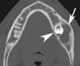

Cystic ameloblastoma

Ameloblastoma is a rare, benign tumor of odontogenic epithelium (ameloblasts, or outside portion, of the teeth during development) much more commonly appearing in the lower jaw than the upper jaw. It was recognized in 1827 by Cusack. [Source: Wikipedia ]